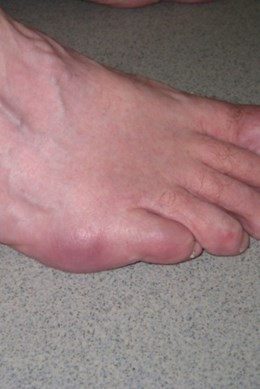

Een bunionette is een pijnlijk uitstekende knobbel net voor de kleine teen.

Het is een pijnlijke knobbel waarbij vaak eeltvorming optreedt. Soms gaat dit gepaard met een kleine teen die over of onder de 4de teen buigt. Schoenen worden hierdoor moeilijker verdragen.